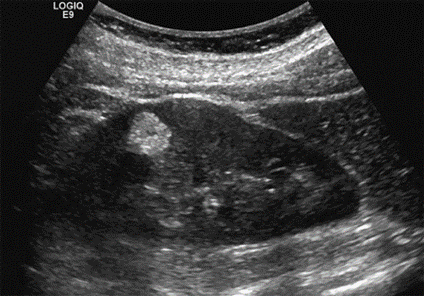

Splenomegaly: The dilated splenic hilum is secondary to portal hypertension, with hepatosplenomegaly.